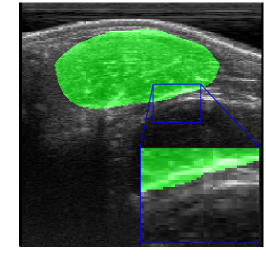

Rib Eye Area (REA). This image dataset consists of ultrasound images of the Longissimus dorsi muscle between the 11th and 13th ribs of cattle. The goal is to automatically calculate the rib eye area (REA), an important region for decision making during cattle breeding. The main challenge is the uncertainty in the REA annotation, since the image is noisy and even experts have difficulty in delimiting the borders of this region. Fig. 3 presents examples of images and the annotation made by a specialist. We can observe that some borders are absent and depend on the subjectivity and knowledge of the annotator. To evaluate the segmentation methods, 76 images with 309×213309213309\times 213 resolution were obtained and labeled by an expert. Due to the number of images, the division of the images in training and testing followed 5-fold cross-validation.

Figure 3: Sample images from Rib Eye Area (REA) dataset.

REA dataset. This image dataset has high uncertainty during labeling due to noise from the ultrasound image. In some cases, the border of REA is not completely visible and must be estimated by the specialist. Therefore, the proposed approach becomes essential to obtain accurate segmentation at the edges. The segmentation examples in Fig. 6 show that the baseline was not able to define the REA correctly due to the uncertainty of the labeling. On the other hand, the proposed approach presents results close to the specialist in regions that the border needs to be estimated.